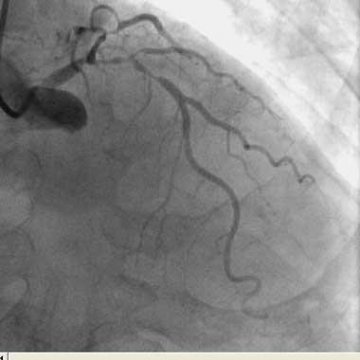

• 严重弯曲的髂动脉、桡动脉、锁骨下动脉及右冠状动脉的TRI策略-看似不可能完成的任务

严重弯曲的髂动脉、桡动脉、锁骨下动脉及右冠状动脉的TRI策略-看似不可能完成的任务

广西医科大学附属第一医院术者:李 浪病例描述:既往病史: 患者莫某,男,88岁因反复活动后胸闷痛2年,加重1月于2006-11-1